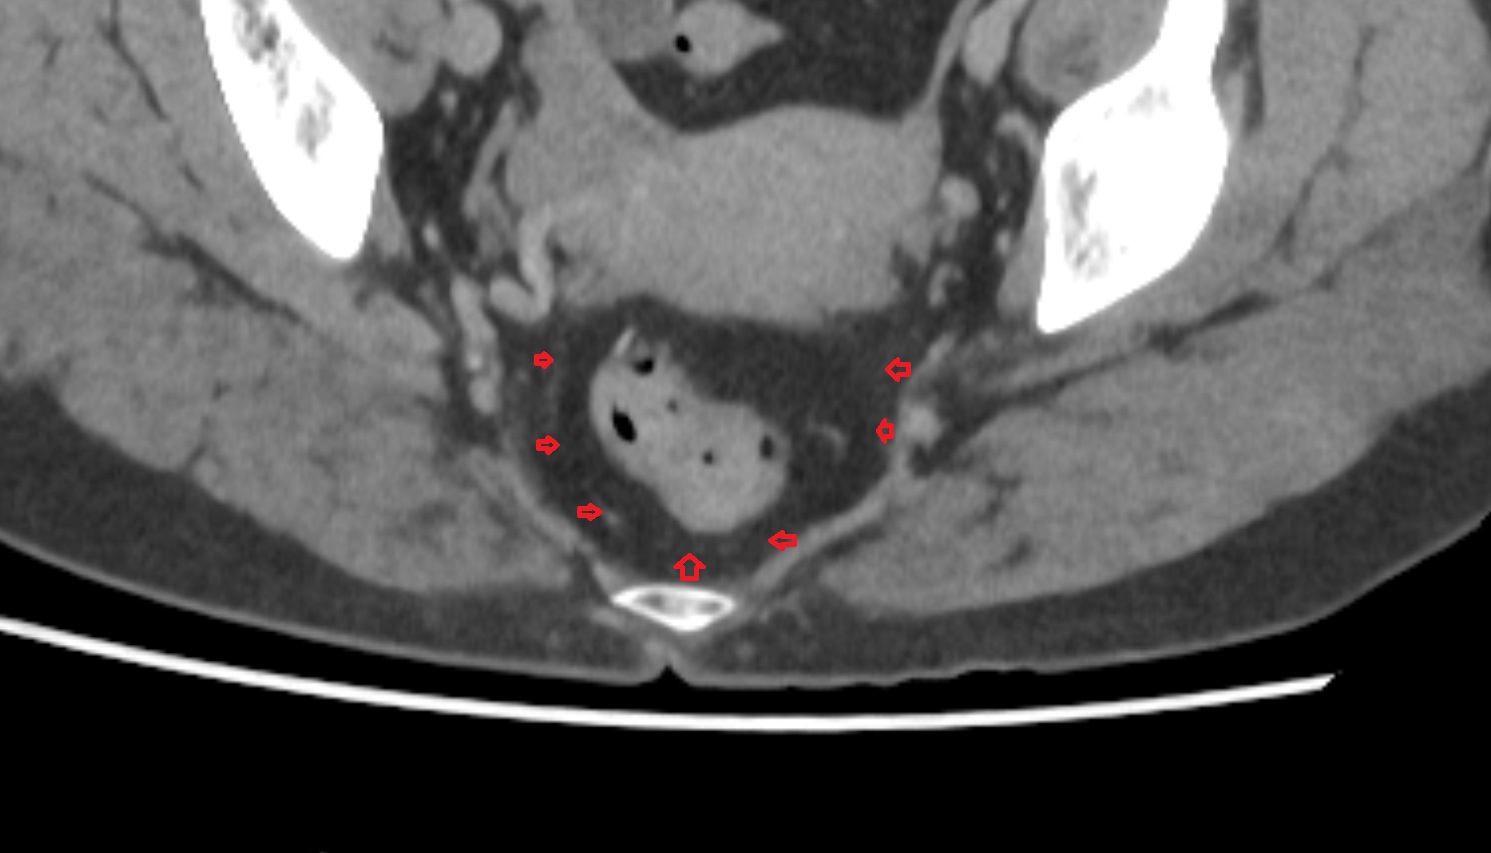

- Mesorectal fascia

- Mesorectum

- Rectum